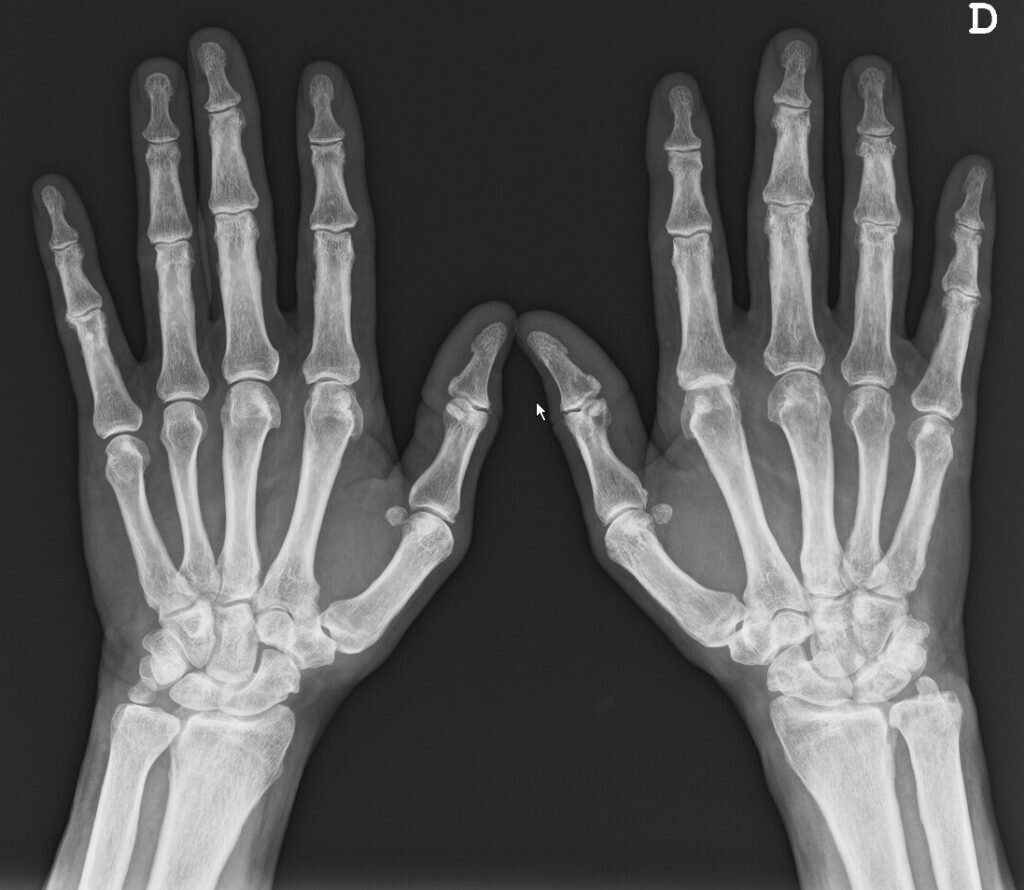

Исследование показало, что существующий препарат эффективен при лечении симптомов остеоартрита рук.

Новое исследование показало, что метотрексат, доступный препарат, который обычно назначают в качестве лечения при ревматоидном артрите, уменьшает боли и скованности остеоартрите рук (ОА). До сих пор не существовало эффективного лечения этого заболевания.

Сотрудники из Университета Монаша и больницы Альфреда в Австралии провели исследование при участии 97 субъектов с ОА рук, осложненным синовитом, выявленным с помощью МРТ. Они получали 20 мг метотрексата или плацебо перорально один раз в неделю в течение шести месяцев.